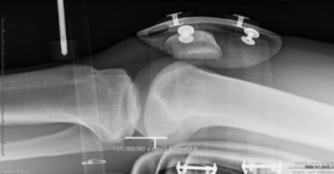

4) RÖNTGENOGRAFIE

Röntgenbild des Knies

Röntgenografie ist auch eine anerkannte Technik zur Analyse des vorderen Kreuzbandes. Das TELOS ist ein berühmtes Gerät, das zur Röntgenbeurteilung von Patienten mit VKB-Verletzungen verwendet wurde, indem die Position der Tibia im Vergleich zum Femur analysiert wurde, während eine einzelne Kraft auf die Tibia ausgeübt wurde.

Die objektiven Ergebnisse, die diese Art der Beurteilung liefert, sind interessant, aber die erforderliche Röntgentechnik macht sie sehr invasiv für den Patienten, weshalb sie auf Platz 4 liegt.